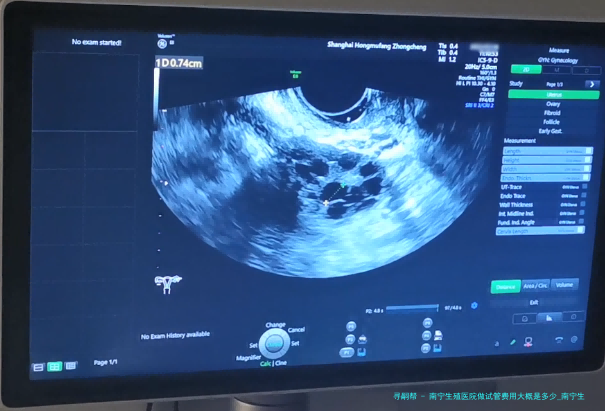

南宁生殖医院做试管费用大概是好多?试管婴儿已然成为许多不孕夫妻实现生育愿望的重要方法其中之一。南宁生殖医院作为专门从事辅助生殖医学的医疗机构,为不孕夫妇提供了精良的试管婴儿服务。如此南宁生殖医院做试管费用大概是几何呢?接下来将细致说明。

在了解详细的试管费用前,我们先来了解一下试管婴儿费用的组成。平常试管婴儿手术所牵涉到的费用囊括下列数个方向:基本治疗费、辅助检查和药品费、手术设备使用费、麻醉师操作费等。

首先是基本治疗费,这片面包括了整个试管过程中所需的医护服务以及专家团队的助力工作。其次是辅助检查和药物费,这部分囊括了对夫妻进行全方位检查所需的各项项目以及实施治疗所需的药品费用。然后是手术设备使用费,这部分囊括了试管婴儿手术所需的各式各样器材和设备的费用。最后是麻醉大夫操作费,这部分包括了在试管手术过程中为患者提供麻醉服务的费用。

南宁生殖医院作为一家专业从事辅助生殖医学的医疗单位,提供了全面而专业的试管婴儿服务。根据不同病人的详细情况和需要,试管费用可能会有所差别。通常来说,南宁生殖医院做试管的基本治疗费大约在5000-10000元之间。辅助检查和药物费、手术设备使用费、麻醉师操作费等其他费用视详尽情形而定。